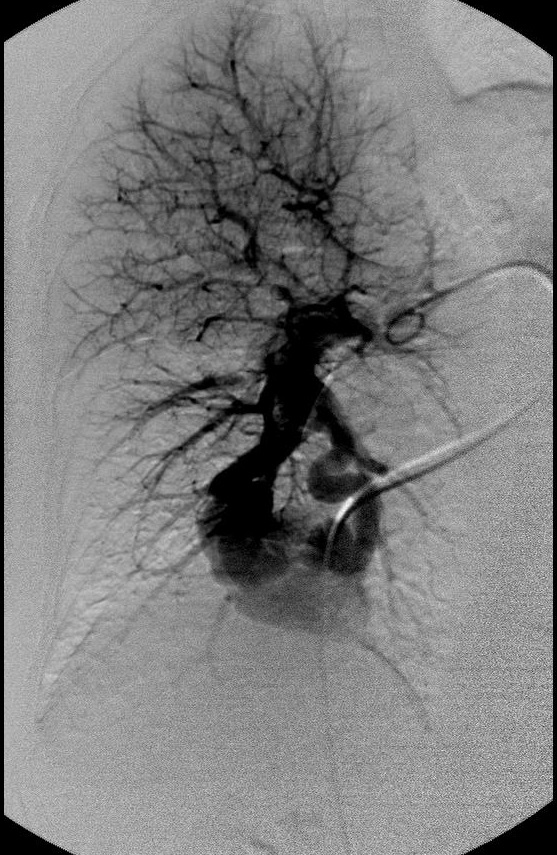

肺动静脉畸形

|

|

|

|

选择其中一支畸形的滋养动脉 |

造影剂经静脉池回流至肺静脉 |

造影剂经静脉池回流至肺静脉 |

|

|

|

|

栓塞开始:先致密填塞静脉池,再致密栓塞滋养动脉 |

造影显示部分静脉池不显影,滋养动脉闭塞 |

选择性肺动脉造影显示另一支滋养动脉和静脉池。 |